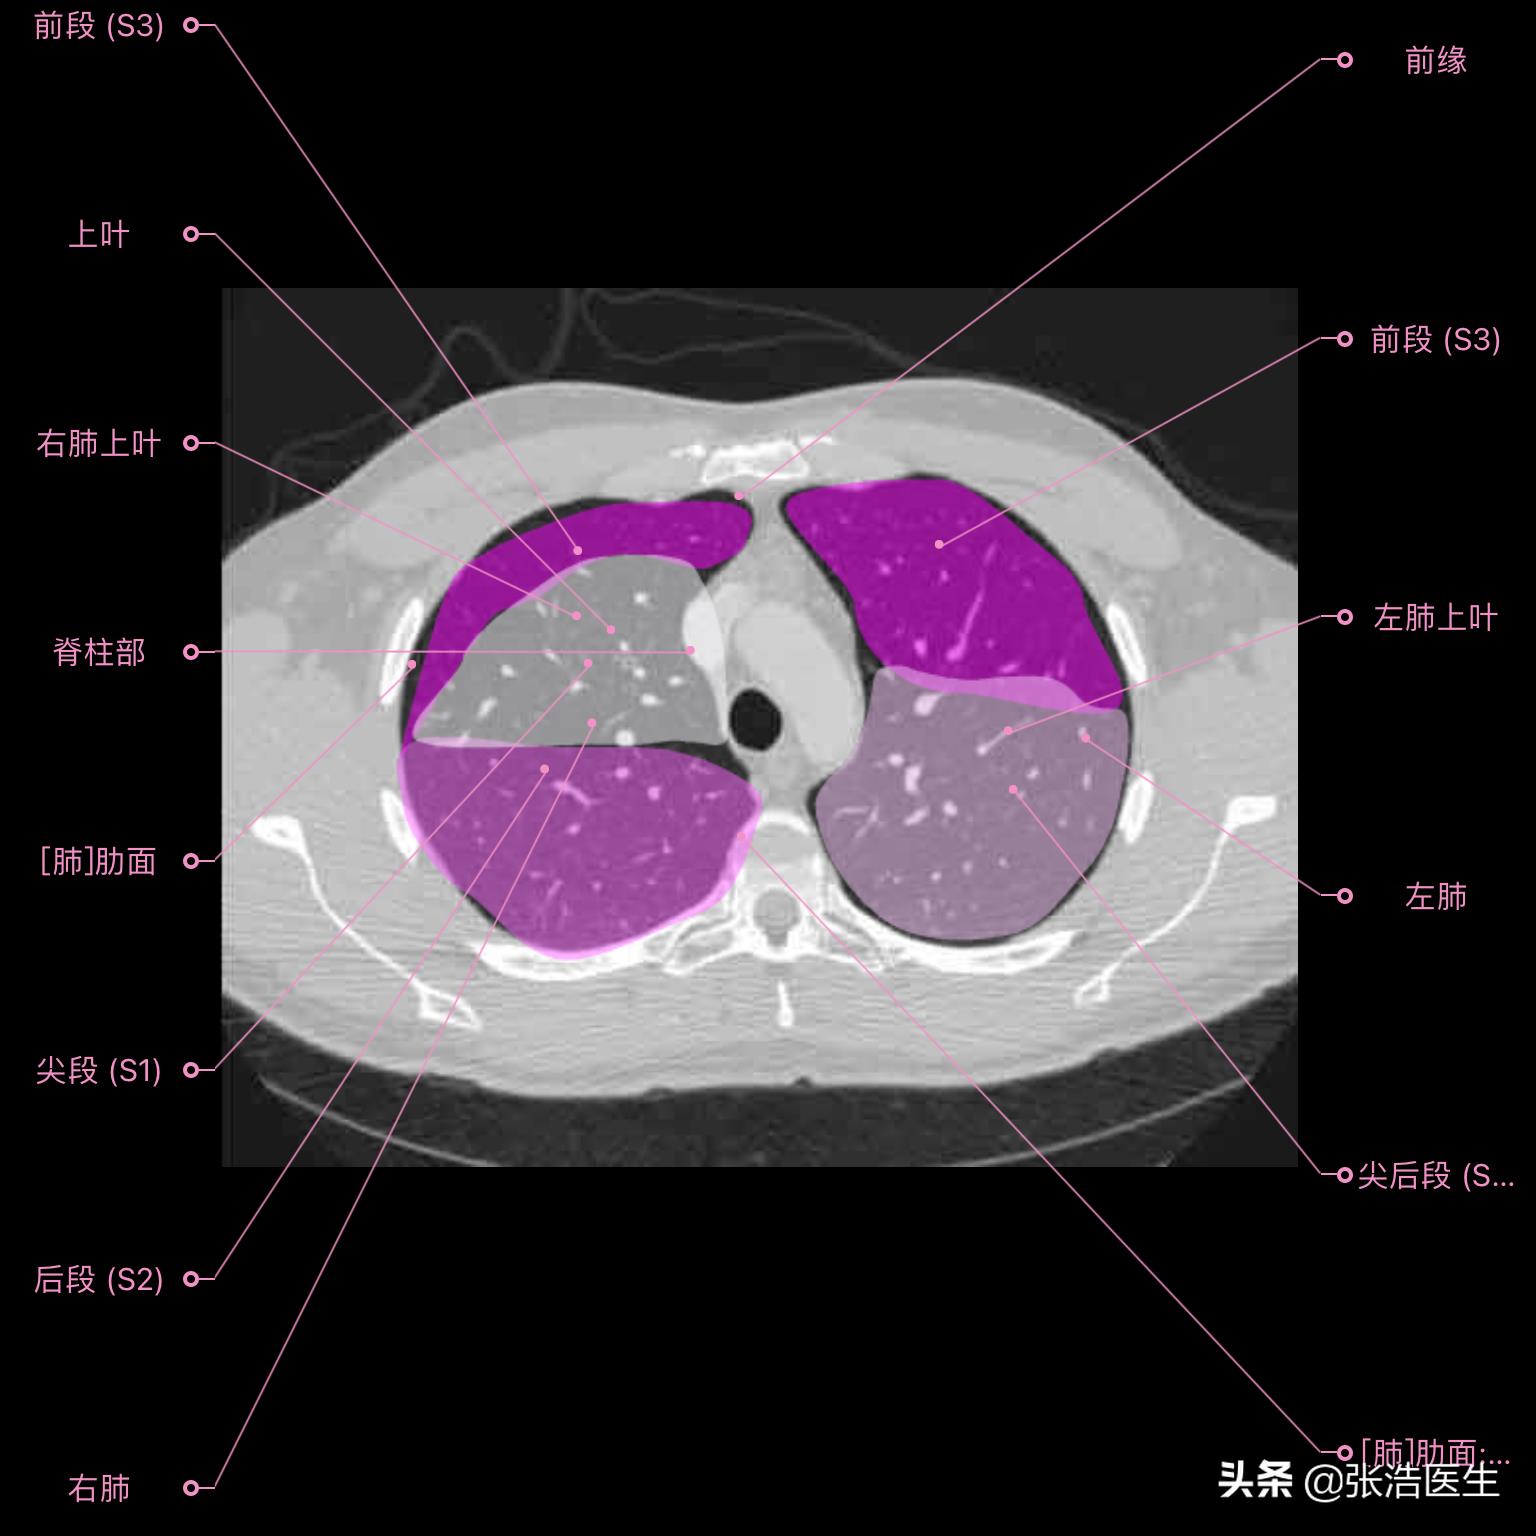

肺部CT横断面高清解剖图谱(图层3)